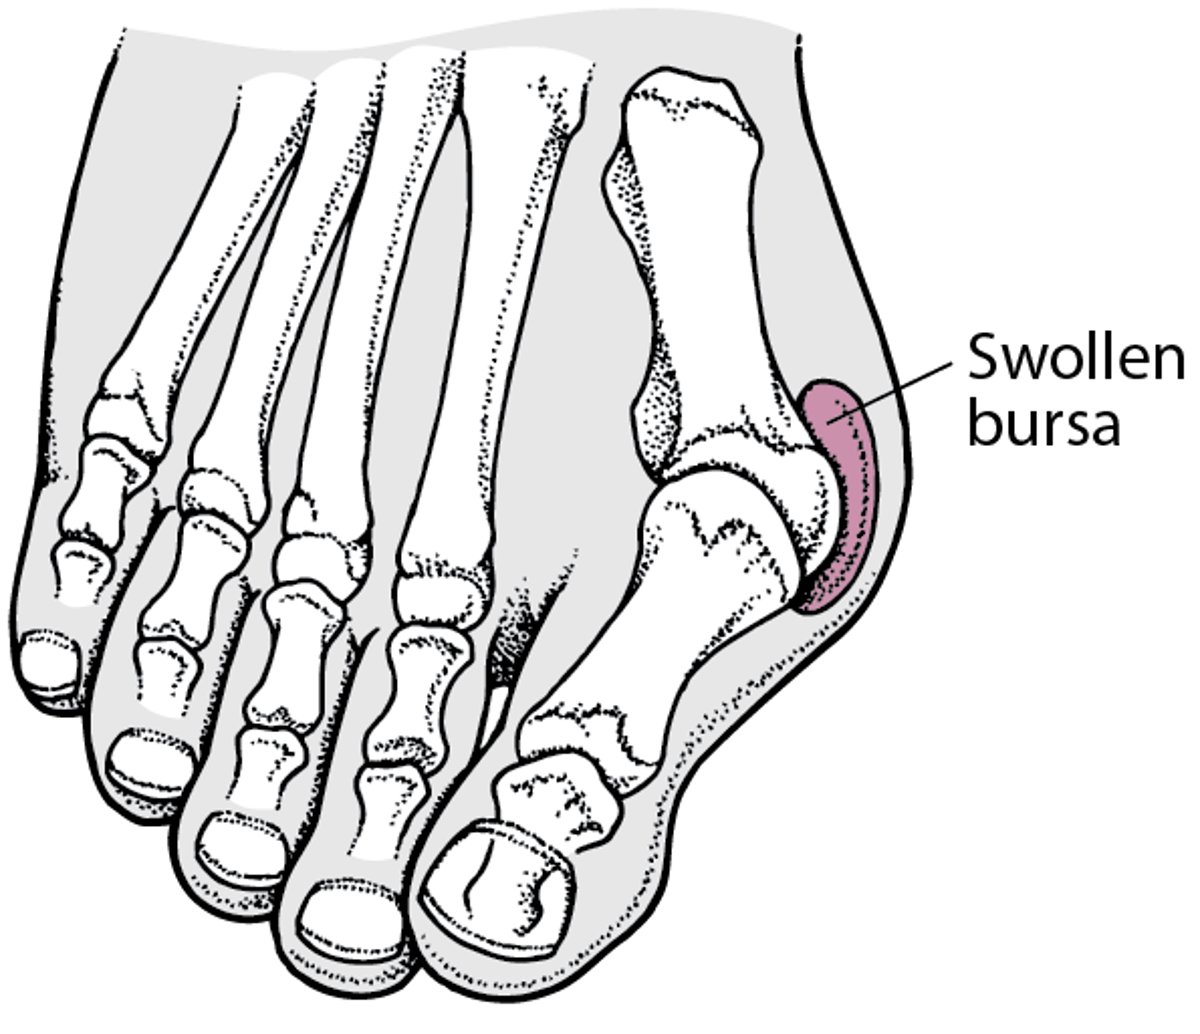

Contributing factors may include a genetic predisposition, excessive foot pronation, wearing tight and pointed-toe shoes, and trauma. Joint misalignment causes osteoarthritis with cartilage erosion and exostosis formation, resulting in joint motion being limited (hallux limitus) or eliminated (hallux rigidus). Mild synovitis may occur, causing joint swelling. Tight footwear can exacerbate symptoms, and an adventitious bursa can develop medial to the joint prominence, which can become painful, swollen, and inflamed (see figure Bunion).

Буніон

A bunion (hallux valgus) is a lateral deviation of the hallux (first toe) on the first metatarsal.